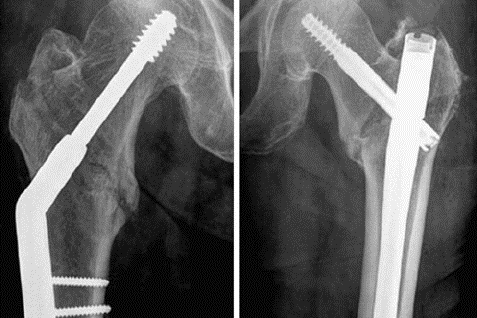

Proximal femur fractures are increasingly common among the elderly population and can lead to significant morbidity and mortality rates. Surgical treatment is the gold standard approach for hip fractures, with the intramedullary nail (IMN) and dynamic hip screw (DHS) being the most commonly used procedures. Despite extensive literature on the biomechanical advantages of both, there are inconsistent findings regarding the comparison of their postoperative clinical outcomes. This study provides a comprehensive analysis of the relative parameters and differences between IMN and DHS treatments in traumatic hip fractures.

Thirty randomized controlled trials with a total of 6,650 patients who sustained hip fractures classified as AO/OTA31A1-A3 were included in this systematic review and meta-analysis comparing surgical fracture fixation with IMN versus DHS. Pooled outcomes of interest included intraoperative differences such as blood loss and screening time, postoperative differences including hospital stays, time to healing, Harris score as well as complications such as femoral neck shortening, non-union, and femoral fractures.

-

A significant difference between IMN and DHS was found with regards to intraoperative parameters such as blood loss and screening time (P<0.0001).

IMN was advantageous in preventing femoral neck shortening (P<0.05) and non-union, however, its shortcomings are open reduction of the fracture and an increased risk of femoral fractures (P<0.0001).

In terms of the postoperative outcomes (hospital stay, time to healing, Harris score, and mobility score) and complication outcomes, there were no significant differences between the two treatment options.

Bottom line. While IMN may offer benefits in terms of blood loss, lower incidence of femoral neck shortening, and improved non-union rates, it is recommended to pay special attention to the risk of femoral fractures during IMN insertion.